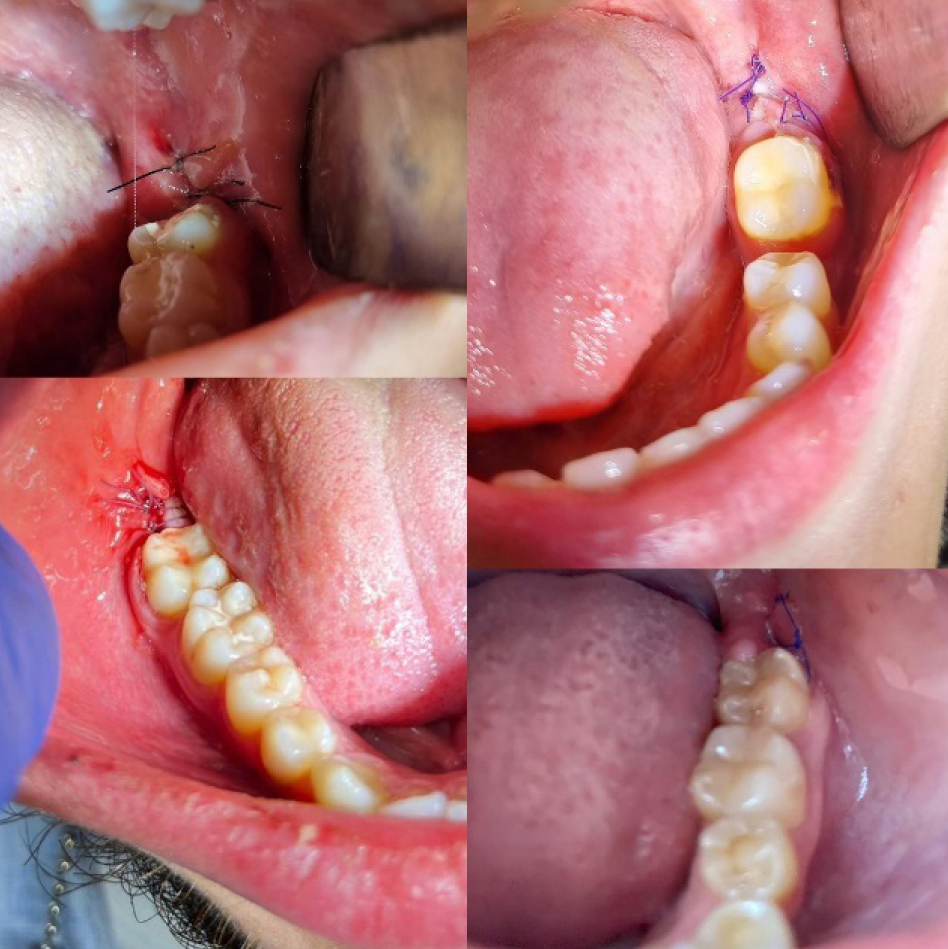

Рис. 1. Конусно-лучевая компьютерная томография

Дополнительные методы обследования включали в себя проведение конусно-лучевой компьютерной томографии (рис. 1), измерение расстояния между центральными резцами нижней и верхней челюсти (рис. 2), для оценки функционального состояния жевательных мышц было проведено электромиографическое исследование.

Всем пациентам проведено обследование, составлен план лечения. Операция атипичного удаления проводилась максимально щадящим способом с отслаиванием слизисто-надкостничного лоскута, трепанацией кортикальной пластинки костной и фрагментацией удаляемого зуба. Операционная рана заполнялась остеопластическим материалом, слизисто-надкостничный лоскут укладывался на место, накладывались узловые швы синтетическим, монофиламентым шовным материалом (рис. 4).

Рис. 4. Состояние лунок удаленных ретинированных зубов